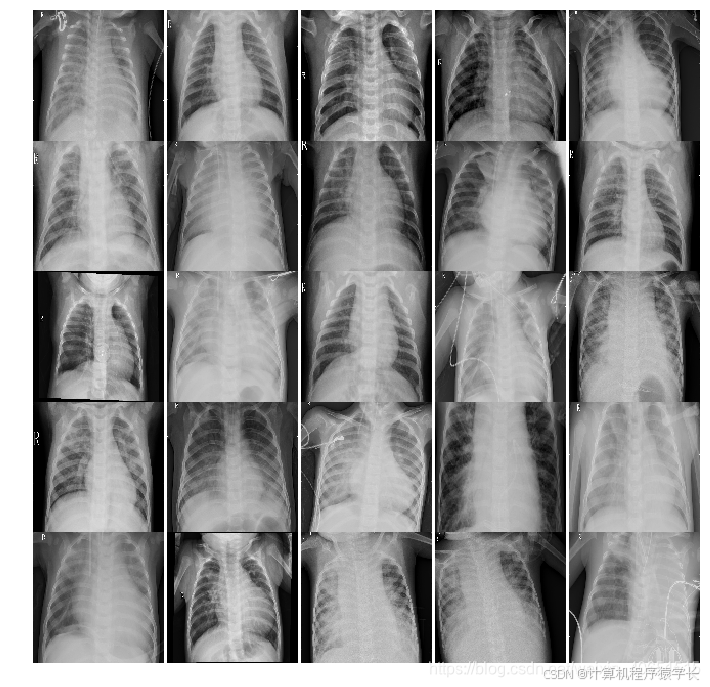

本文主要基于kaggle数据集(胸部X射线照片)进行肺炎疾病的识别与预测。主要将探索两部分内容:

一是:通过训练深度学习模型(多层CNN模型),使CNN能够根据患者胸部的X射线图像检测患者是否患有肺炎疾病。